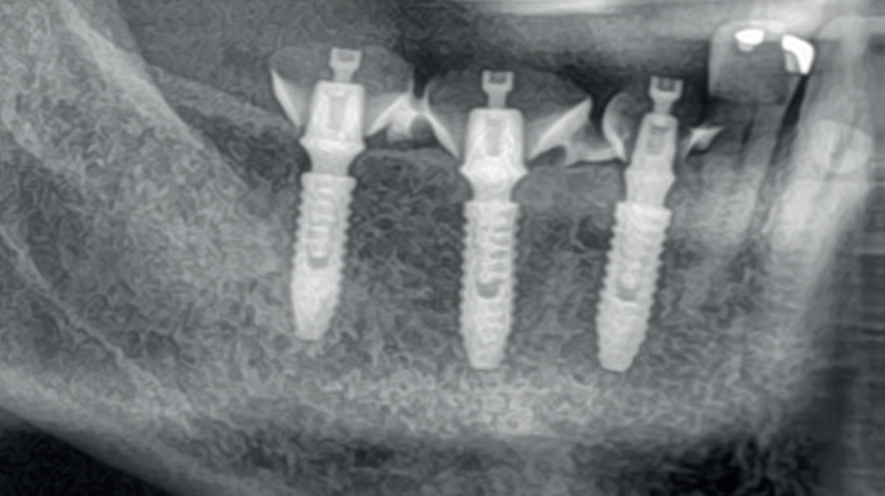

A Prótese Dentária na era digital ganhou novas perspectivas, tornando os procedimentos protéticos mais rápidos, precisos e eficazes. Entretanto, as etapas de planejamento e de transição entre a instalação dos implantes e das coroas protéticas permanecem decisivas para que os resultados almejados sejam atingidos.

A restauração protética esteticamente agradável de um implante requer a criação de um adequado perfil de emergência da mucosa peri-implantar, que é a transição entre o implante e a coroa protética. Quando corretamente explorado, proporciona uma suave transição da plataforma circular do implante para a anatomia natural do dente. Quanto mais detalhados forem estes processos, maiores serão as chances de sucesso dos tratamentos protéticos reabilitadores.

Ao serem instalados, os implantes que atingem um torque de inserção ≥ 32 Ncm podem ser imediatamente carregados com coroas unitárias de transição não oclusivas. Abaixo deste torque, ou em situações onde não desejamos correr riscos, em vez de uma coroa de transição, instala-se um cicatrizador personalizado contendo um perfil transmucoso com as mesmas características que a coroa provisória teria. Os objetivos dos cicatrizadores customizados nos casos de instalação do implante imediatamente após a exodontia são: selar o sítio cirúrgico respeitando o perfil do alvéolo de extração, estabilizar o coágulo sanguíneo e favorecer a regeneração óssea com o material substituto, evitar o colapso de tecidos moles durante o período de cicatrização e desenvolver um perfil de emergência protético ideal para a futura coroa sobre implante, baseado na anatomia do dente natural extraído, sem receber carga oclusiva.

Nos casos de instalação de implantes em regiões edêntulas, também é possível empregar cicatrizadores personalizados, desenvolvendo um perfil de emergência protético ideal para a futura coroa sobre implante, baseado na anatomia do dente natural ausente. Os dois procedimentos restabelecerão o perfil de emergência original do paciente durante a fase de cicatrização/osseointegração dos implantes, devolvendo a harmonia dentogengival, com a recuperação das papilas interdentais e a reconstituição do arco gengival côncavo, com altura adequada da margem em relação aos dentes adjacentes.